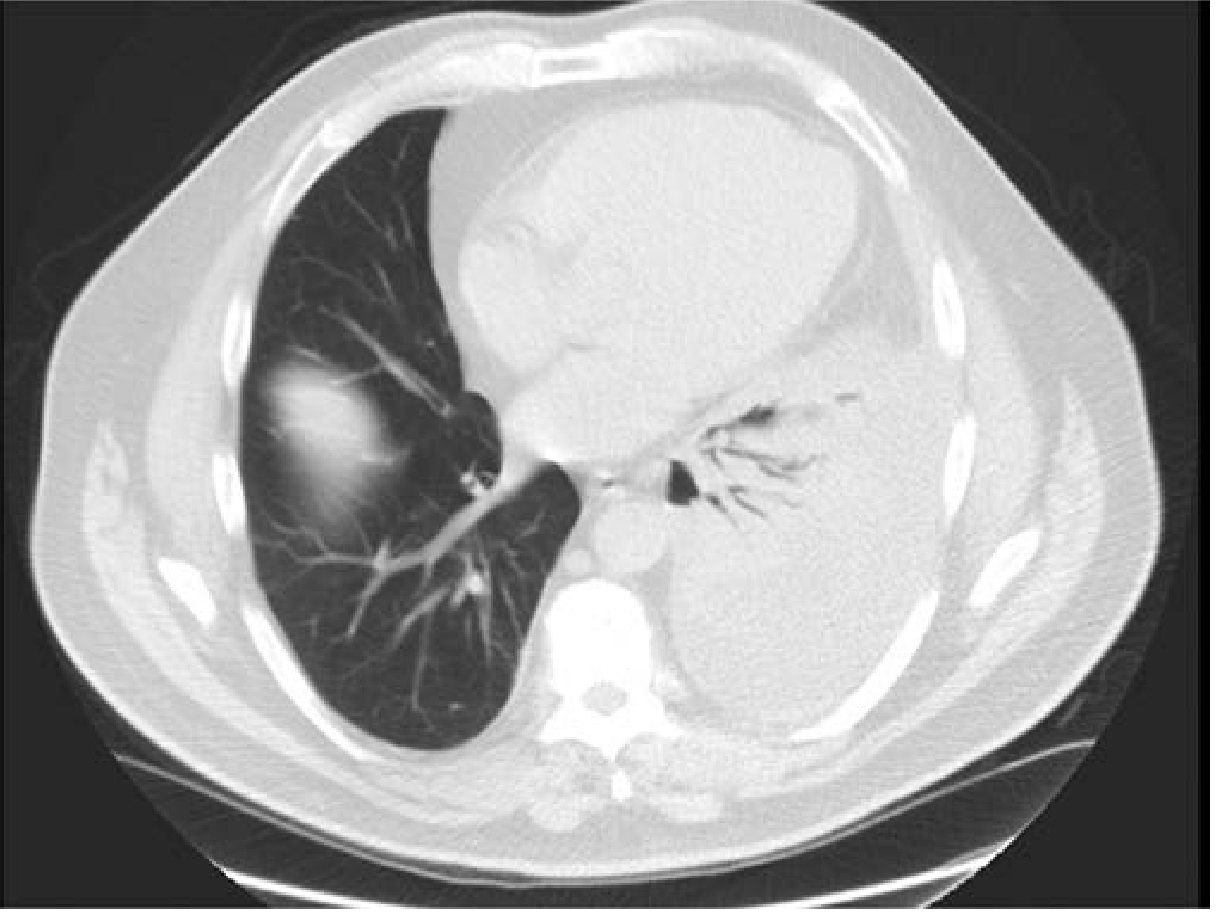

Imaging features

• Lobar air-space consolidation on chest imaging

• Air bronchograms are a classic clue (air-filled bronchi outlined by surrounding alveolar opacification)

• Pleural effusion may accompany severe bacterial cases

(Fishman’s Pulmonary Diseases and Disorders, p. 1640)

CT appearance of lobar pneumonia with air bronchograms